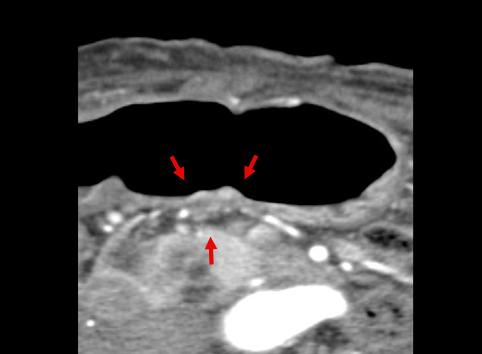

A case of 0-IIa+IIc type early gastric cancer with prominent lymphoid infiltration.

[ Image ID:11410 ]

Malignant epithelial tumor/Adenocarcinoma

Stomach/Angle

CT

Type 0/IIa (IIa+IIc) Superficial elevated and depressed type

15 - 19

submucosa